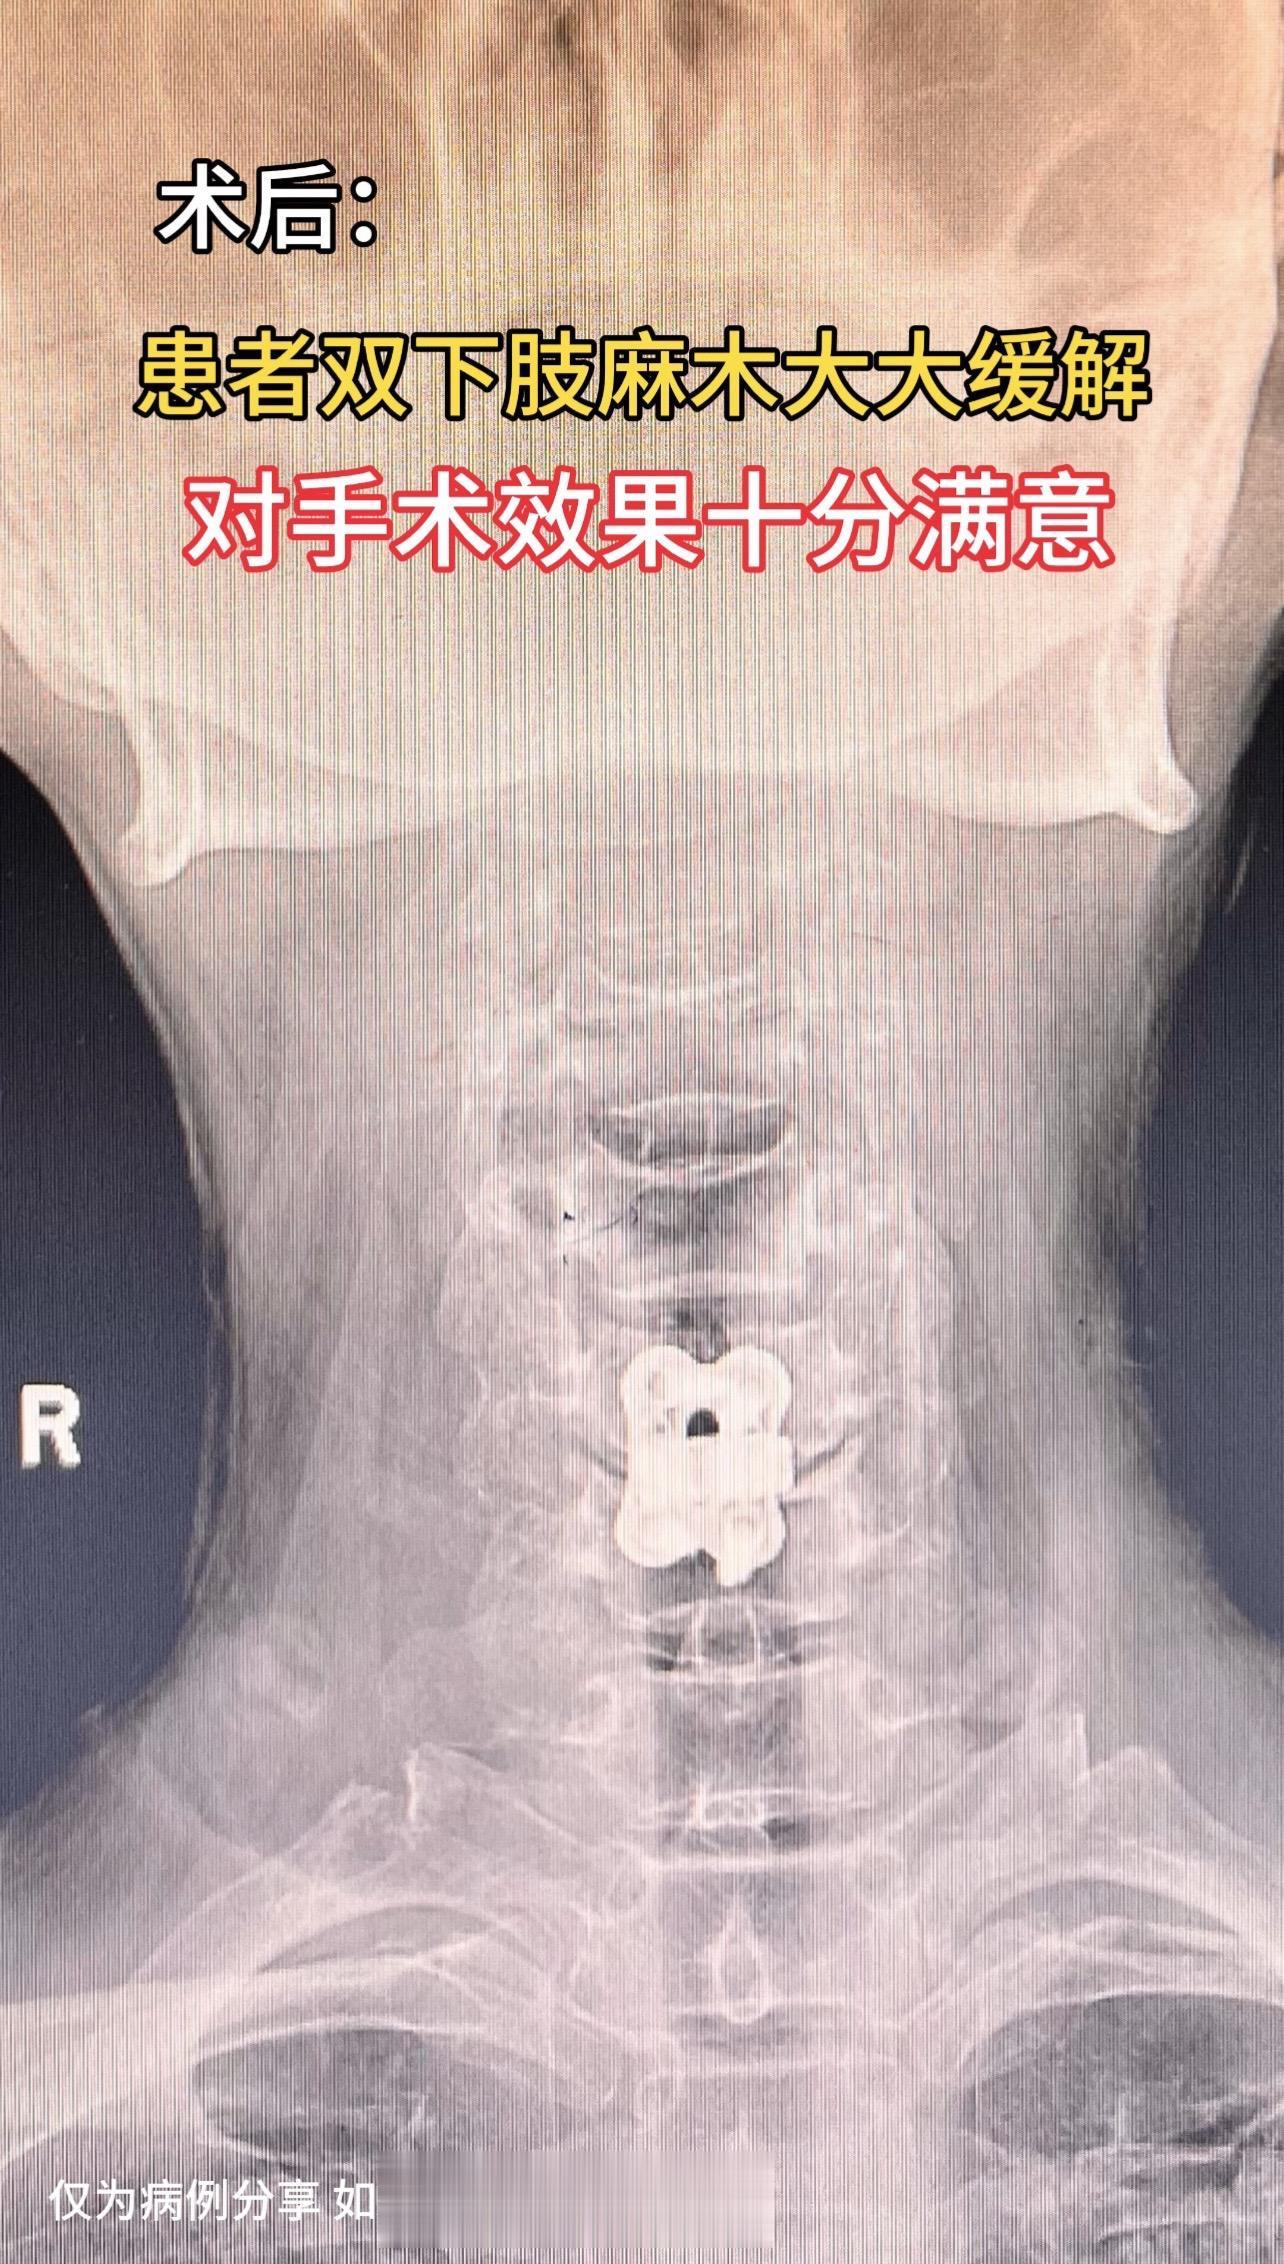

50岁女性,四肢麻木3年加重1年,双下肢重,偶有下肢踩棉花感。患者感觉很痛苦,看了好多医院,片子看着并不太重。2个月前在我科行保守治疗,效果差。后建议去北京协和会诊,协和说有手术指征,但不大。患者又返回我院,要求手术治疗,与患者沟通手术效果欠佳可能性大,但患者仍坚持手术治疗。术后患者双下肢麻木大大缓解,对手术效果十分满意。患者的理解信任是我们前进的动力源泉。